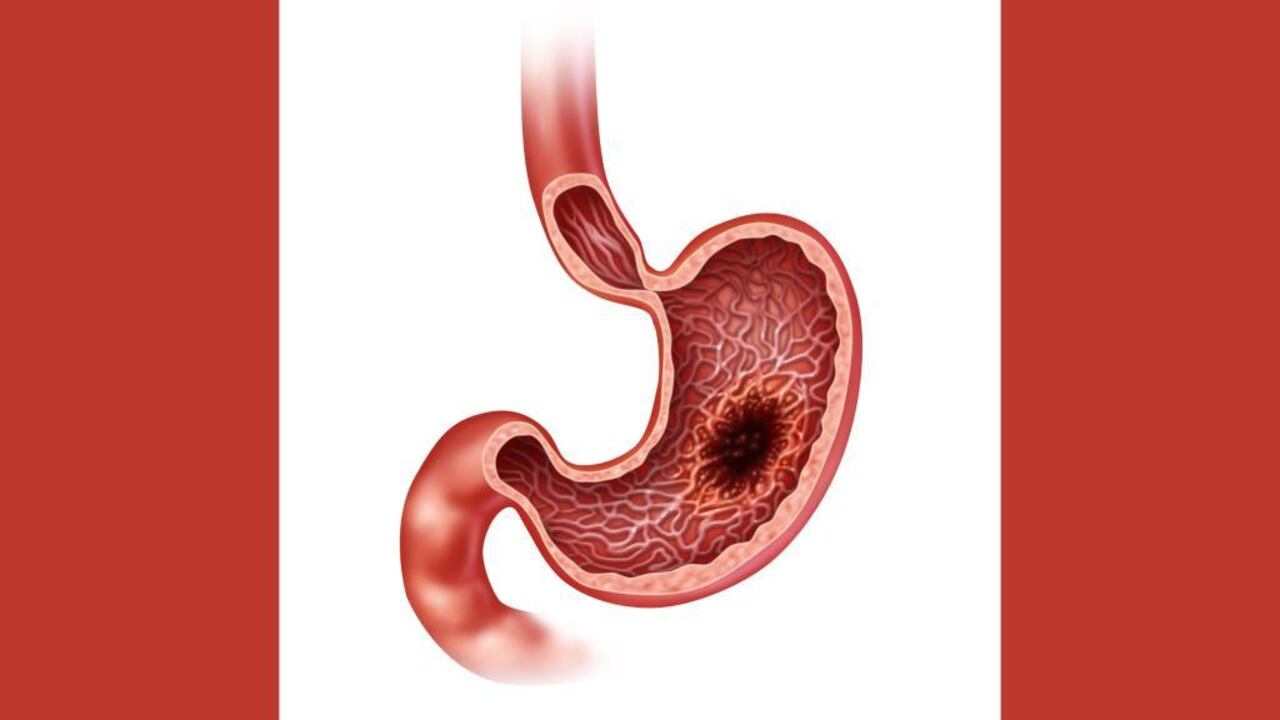

Este es el tipo de cáncer que genera heces de color negro

Uno de los tipos de cáncer más comunes es el de estómago, al cual también se le denomina cáncer gástrico o estomacal. Es una enfermedad que se origina en los tejidos que revisten este órgano que se encuentra ubicado del lado izquierdo, en la parte superior del abdomen y que participa en la digestión de los alimentos.

La Biblioteca Nacional de Medicina de Estados Unidos indica que es difícil diagnosticar el cáncer de estómago en sus primeras etapas. La indigestión y la molestia estomacal pueden ser síntomas de una etapa temprana del cáncer, pero otros problemas también pueden causar los mismos síntomas.

En los casos avanzados los principales síntomas son los siguientes, de acuerdo con el instituto de investigación Mayo Clinic.

- Dificultad para tragar

- Heces de color negro

- Dolor abdominal

- Sensación de hinchazón abdominal después de comer

- Sensación de saciedad después de comer cantidades pequeñas de comida

- No tener hambre cuando se espera tenerla

- Acidez estomacal

- Indigestión

- Náuseas

- Vómitos

- Pérdida involuntaria de peso

- Sentirse muy cansado